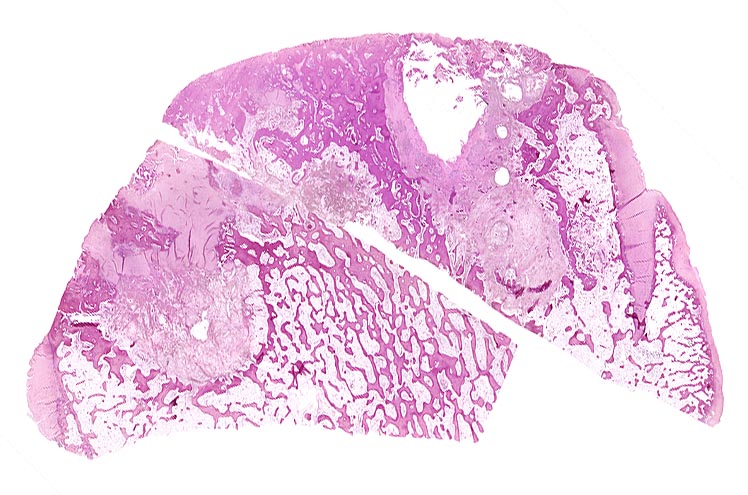

• Deformierte Gelenkfläche.

• Weitgehendes Fehlen des hyalinen Gelenkknorpels.

• Sekundäre Sklerose der freiliegenden Spongiosa mit Anbau von breiten Faser- und Lamellenknochensäumen an die alten Bälkchen.

• Leichte Osteoporose in der craniolateralen Entlastungszone.

• Herde von metaplastischem Faserknorpel in der Gelenkfläche.

• Randosteophyt, welcher über Resten des dort noch vorhandenen Gelenkknorpels entstanden ist (Verdoppelung des Knorpels).

• Nekrosebezirk in der Spongiosa (Geröllzyste) umgeben von einem Granulationsgewebssaum und Narbengewebe.